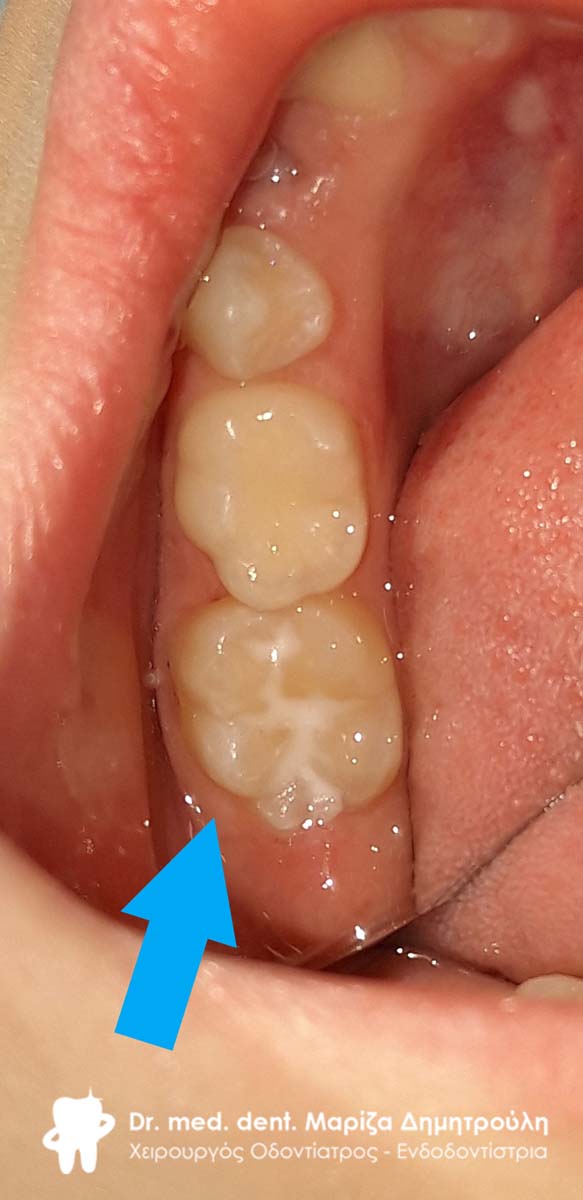

Στα πλαίσια του ετήσιου προληπτικού οδοντιατρικού ελέγχου πραγματοποιήθηκε στο μικρό ασθενή προληπτική κάλυψη οπών και σχισμών (sealant) στον πρώτο αριστερό μόνιμο γομφίο της κάτω γνάθου.

ΠΡΙΝ

ΜΕΤΑ